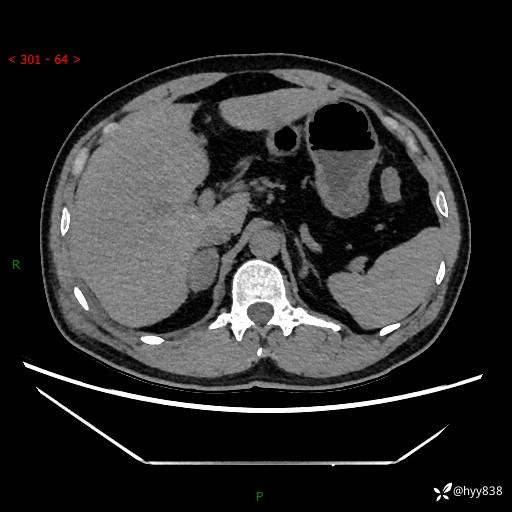

现病史:患者9月4日摔伤在深圳市宝安区中心医院行CT检查提示右侧肾上腺区结节(38*27mm),复查B超提示右侧肾上腺区可见一61*24mm异常低回声团,建议进一步检查。进一步完善增强CT后提示:右侧肾上腺区肿块及周围渗出改变,大致同前,考虑肾上腺腺瘤,不除外瘤内出血可能,否认阵发性头晕、头痛、出汗、乏力等不适,门诊以“ 右侧肾上腺肿瘤”收入住院。 起病来,患者精神、食欲、睡眠可,大便通畅,小便如上述,体力体重无明显改变。

肾上腺CT平扫

增强(动脉期+静脉期)